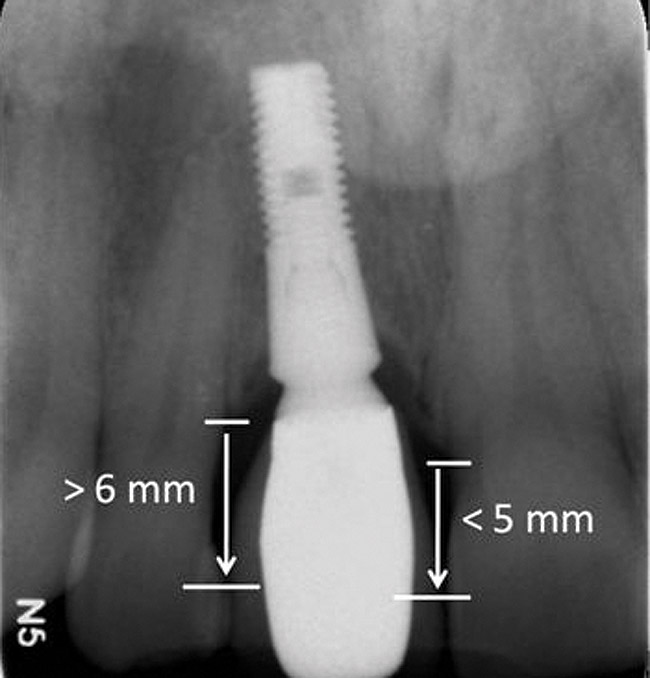

Figure 4  Characterization of the interproximal bone and tooth contacts: A periapical radiograph assists in measuring the distance from bone crest to the adjacent tooth contact points for missing tooth No. 8. The mesial bone crest to the adjacent tooth contact distance is < 5 mm, while the distal bone crest to adjacent tooth contact distance is > 6 mm (Fig 4). One-year following implant placement, conservation of these dimensions is revealed (Fig 5). The clinical photograph (Fig 6) of the lateral incisor adjacent to tooth No. 8 implant crown demonstrates that the absence of distal interproximal (papilla) fill related to the observed bone crest to contact distance exceeds 6 mm.

Figure 4

Figure 5  Characterization of the interproximal bone and tooth contacts: A periapical radiograph assists in measuring the distance from bone crest to the adjacent tooth contact points for missing tooth No. 8. The mesial bone crest to the adjacent tooth contact distance is < 5 mm, while the distal bone crest to adjacent tooth contact distance is > 6 mm (Fig 4). One-year following implant placement, conservation of these dimensions is revealed (Fig 5). The clinical photograph (Fig 6) of the lateral incisor adjacent to tooth No. 8 implant crown demonstrates that the absence of distal interproximal (papilla) fill related to the observed bone crest to contact distance exceeds 6 mm.

Figure 5

Additional attention must be paid to the osseous architecture related to the adjacent teeth, as this controls interproximal tissue form.7 The crest of healthy bone is 4.5 mm to 5 mm from the contact point between anterior teeth8; a similar 5-mm distance from the contact point to the bone crest has been measured between an implant and natural tooth. An important and additional rule to guide esthetic implant outcomes is that the adjacent tooth should possess interproximal bone levels no further than 6 mm from the natural tooth contact point (Figure 4 through Figure 6). While the ideal distance is justifiably indicated to be 5 mm, this 6-mm rule establishes a point at which marked interproximal tissue deficiencies and asymmetry will not be overcome.